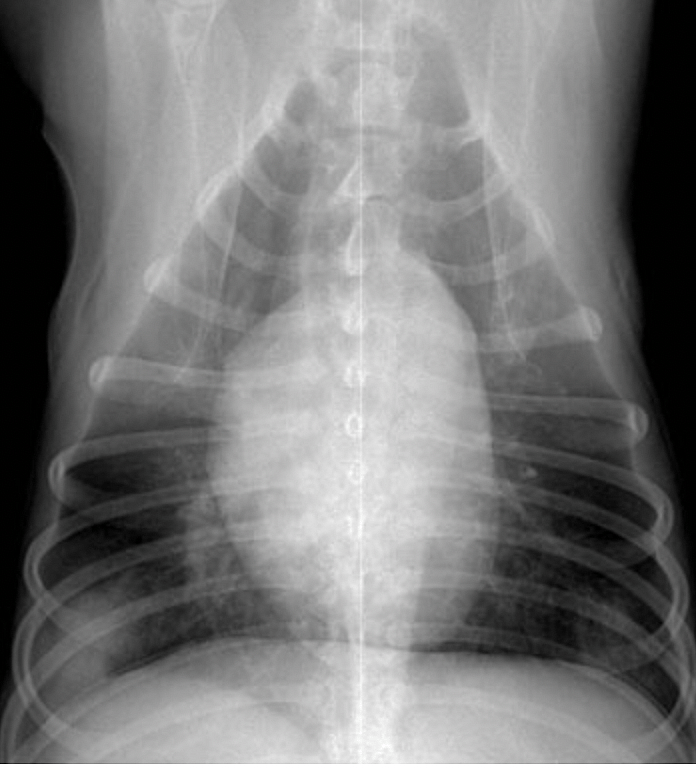

Before Sage even got a chance to settle into her forever home with Sharon, things went from bad to worse and Sage began to bleed vaginally. Sage was diagnosed with a cancerous tumor called a canine transmissible venereal tumor (CTVT), but that wasn’t all. The 1.5-year-old Black Mouth Cur mix had also contracted valley fever (coccidioidomycosis) and tick fever, AKA Rocky Mountain spotted fever.

Removing Sage’s tumors didn’t completely get rid of the cancer, but there were still more options. Luckily, Sage’s prognosis was good, since canine transmissible venereal cancer is one of the most common and curable forms of cancer in dogs. Sage was enrolled in chemotherapy, and after just three rounds, she was cancer-free!

Valley fever is caused by inhaling Coccidiodes immitis fungal spores, which are common outdoors in dirt and dust. Common symptoms of valley fever in dogs include coughing, fever, unwanted weight loss, lack of appetite, and lethargy. If the infection becomes serious, it can lead to far more life-threatening issues like seizures, brain swelling, and even heart failure.